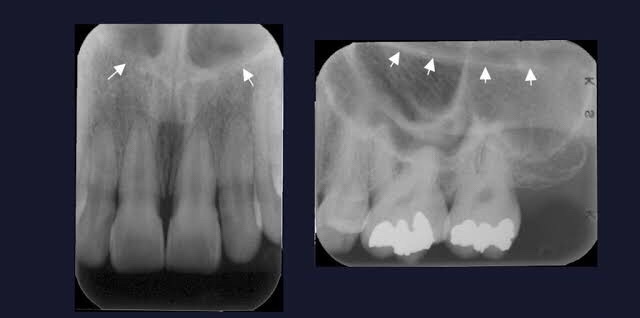

• Nasal fossa – The nasal fossae are the nasal openings located above the maxillary anterior teeth. Radiographically, the nasal fossae appear as vertically oblong radiolucent structures bounded by bone.

• Anterior Nasal spine – Located at the anterior & inferior portion of Nasal cavity situated in the midline. Appears as a V-shaped or triangular radiopacity.

• Nasal Septum – Vertical bony wall that divides the nasal cavity into right & left fossae formed by Vomer & ethmoid bone.

• Nasal cavity – Pear shaped, air filled conpartment of bone located superior to maxilla, appears as radiolucent area.

• Floor of nasal cavity – Bony wall formed by palatal process of Maxilla & horizontal portion of palatine bone. Appears as dense radio-opaque band that cuts the maxillary process.

• Y line of Ennis – The inverted Y is a radiographic landmark that depicts where the nasal fossa crosses the maxillary sinus. The boundary between them is shaped like an upside-down letter Y, hence its name.